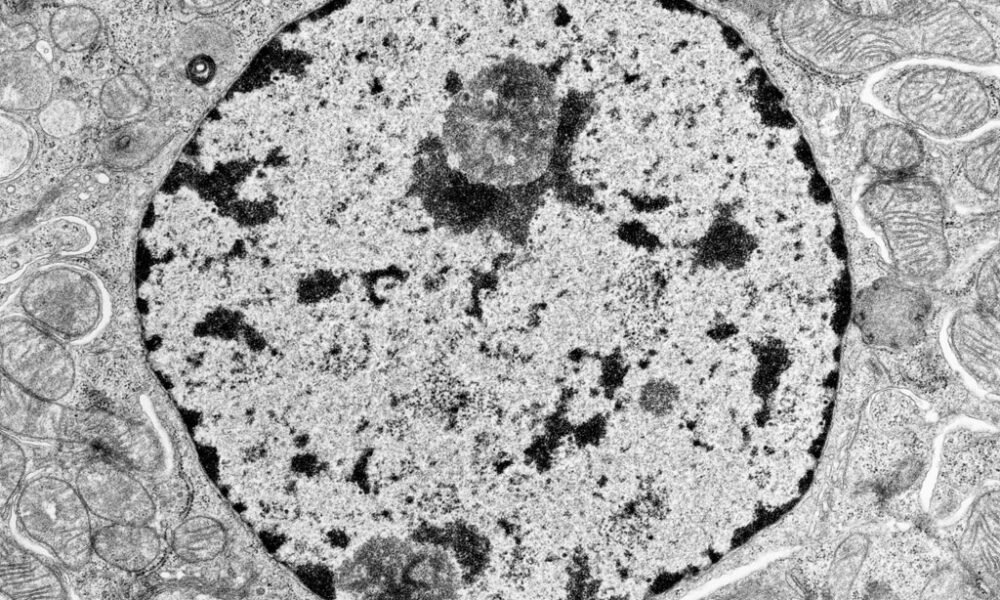

In this article we will discuss about the functions of the neuroglia Functions of the Neuroglia 90% of the central nervous system is made up of...